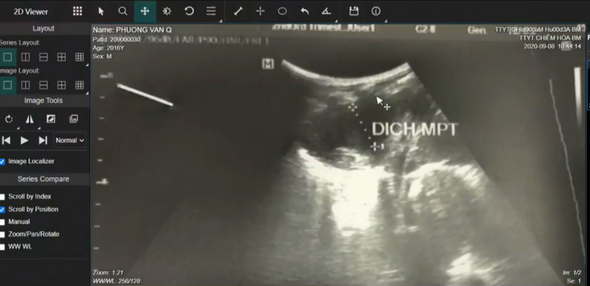

Hình ảnh siêu âm khu vực phổi của bệnh nhân 4 tuổi ở Chiêm Hóa. Ảnh: Tư liệu của Bệnh viện Bạch Mai.

TTYT huyện Chiêm Hóa cho biết, bệnh nhân P.V.Q (4 tuổi, trú tại xã Trung Hòa, huyện Chiêm Hóa) nhập viện ngày 7/9/2020, do đau ngực trái. Bệnh nhân được chẩn đoán tràn dịch màng phổi, viêm phổi.

Mở đầu buổi hội chẩn từ xa, TTYT huyện Chiêm Hóa (tỉnh Tuyên Quang) đã báo cáo và xin ý kiến hội chẩn, điều trị cho nam bệnh nhân 4 tuổi nhập viện do tràn dịch màng phổi, viêm phổi.